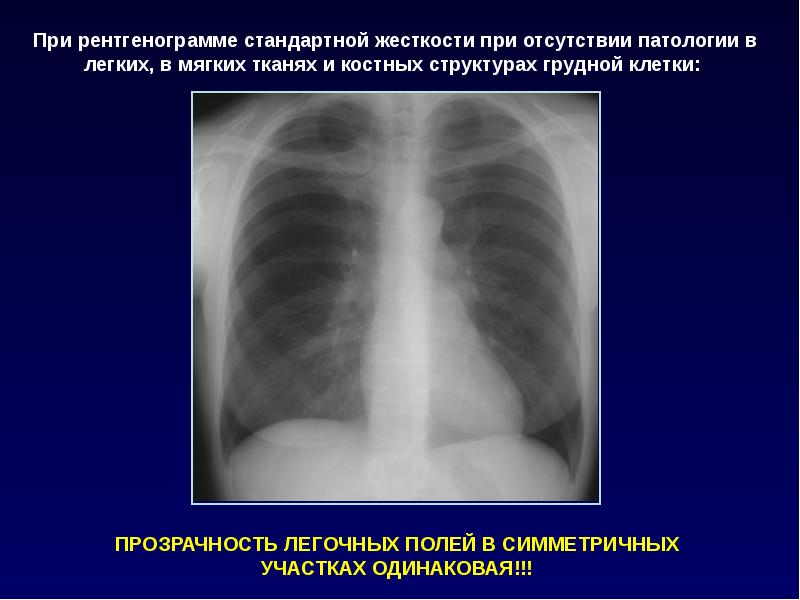

Рентгенологические изображения и синдромы патологии легких

Раздел: Кадры-подсказки